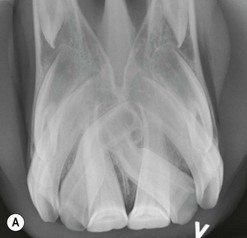

image image

Fig. 8.8 (A) Intra-oral radiograph of a premaxilla containing two bent, supplemental supernumerary (permanent) incisors lying at oblique angles, that have caused overcrowding and displacement of the remaining incisors. (B) One of these supernumerary incisors is visible, abnormally protruding at an oblique angle between 201 and 202.

Because of their normal morphology, supplemental supernumerary incisors can readily be confused with retained deciduous incisors. This is particularly the case with larger retained incisors, whose permanent successors erupted beside, rather than beneath, the deciduous incisor, and thus have not caused any resorption or mechanical displacement of the apex or reserve crown. Radiography usually distinguishes between a retained deciduous and supernumerary incisor, as a retained deciduous incisor is shorter and narrower than a supernumerary permanent incisor (see later), in contrast to supernumerary incisors that are usually of similar size (Fig. 8.8). Supernumerary incisors may cause overcrowding and displacement of the normal permanent incisors, and diastemata often occur beside the displaced incisors. A rostrally displaced supernumerary incisor may also develop between, and so cause separation of the normal incisors (Fig. 8.7).

Supernumerary incisors and possibly displaced normal incisors can erupt in an overcrowded manner along the normal incisor arch, and caudal (palatal) to them on the rostral aspect of the hard palate. In addition to the difficulty in clinically differentiating supplemental supernumerary incisors from normal incisors, it is usually very difficult to extract such displaced supernumerary incisors without causing damage to the remaining incisors, the hard palate and overlying soft tissues. Lateral and intra-oral radiographs generally demonstrate the great length of the reserve crowns of both the normal and the (indistinguishable) supernumerary incisors that are lying closely together, sometimes in an intertwined manner (Fig. 8.8). As the consequences of leaving multiple supernumerary incisors in are usually minimal, these teeth are, therefore, best not extracted. As the supernumerary incisors erupt, their occlusal surfaces are usually worn down by attrition – due to contact with food and intermittent contact with lower incisors due to the normal rostrocaudal movement of the mandible. If, however, supernumerary incisors are extremely displaced, individual teeth lose occlusal contact and overgrow. Such teeth should be reduced biannually, preferably using motorized equipment.